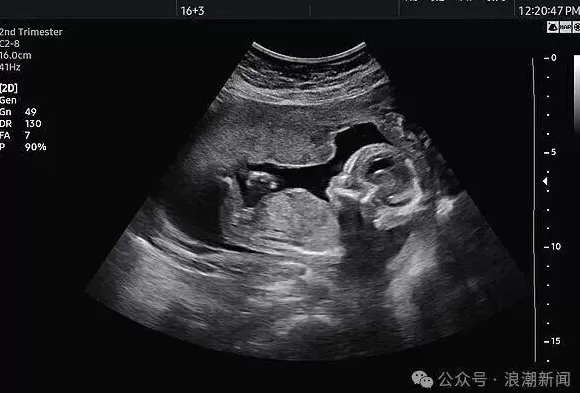

" 来拍四维宝宝照片,店里会送粉蓝相框,盲盒已开,看得很准 ……" 当下,一种 " 胎儿摄影 " 渐渐流行起来,成了新的时尚。许多准爸妈选择 " 胎儿摄影 " 机构,为肚子里的孩子拍 B 超照片留念,而机构也会送出 " 粉蓝 " 礼物,暗示胎儿性别。这类机构是否合规?" 胎儿摄影 " 行为又是否合法?

检察官找到了一名消费者,她表示通过某社交 APP 加入了孕妇群,获悉该孕婴摄影店能为 17 周至 34 周孕妇提供拍摄婴儿照片的服务。她曾于 2024 年 8 月前往该店拍摄,店主用一台类似医院 B 超机的仪器为其拍摄宝宝动态影像,并暗示 " 宝宝很可爱,可以买粉色的衣服 "。

与此同时,该店使用 B 超机的行为也可能涉嫌违法。《关于严禁非法使用超声诊断仪开展 " 胎儿摄影 " 活动的通知》规定,根据《医疗器械分类目录》规定,超声诊断仪属于第二类、第三类医疗器械,适用范围为医疗机构临床诊断。非医疗机构不得使用超声诊断仪。该店并非医疗机构,使用的超声诊断仪来源不明、质量不明,操作设备的工作人员是否有资质、操作是否规范同样不明,可能会对孕妇和胎儿的健康产生一定影响。